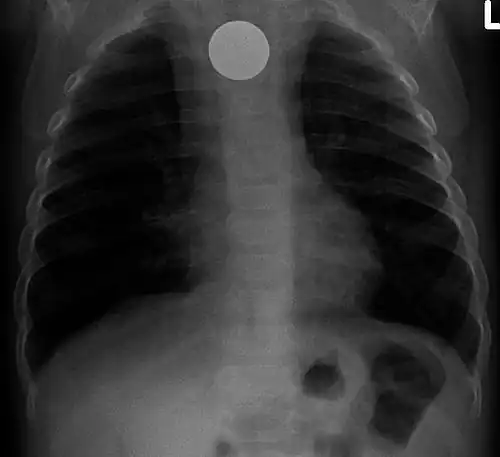

Chest radiograph showing a Venezuelan 25 cent coin lodged in the upper esophagus of a 9-year-old girl. -

If the person who swallowed the foreign body is doing well, usually an x-ray image will be taken which will show any metal objects, and this will be repeated a few days later to confirm that the object has passed all the way through the digestive system. Also it needs to be confirmed that the object is not stuck in the airways, in the bronchial tree.